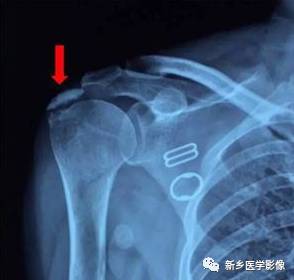

病例三:

红色箭头:肱骨头后方骨缺损(Hill-sachs损伤)

黄色箭头:关节盂前下方Bankart损伤